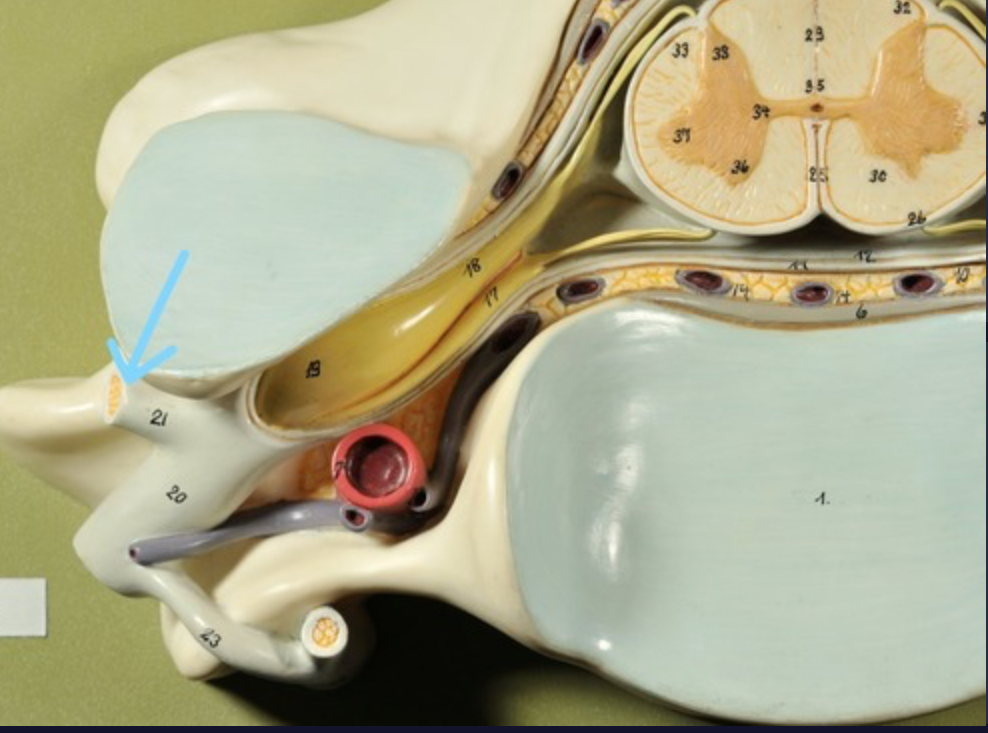

Dura mater (outermost layer)

White matter of spinal cord

Gray matter of spinal cord

Ventral horns (of gray matter)

Lateral horns

Dorsal horns

Anterior columns of white matter

Lateral columns of white matter

Posterior columns of white matter

central canal of spinal cord

Pia matter

Subarachnoid space

Arachnoid matter

Subdural space (brown line)

Dura matter

Epidural space

Dorsal root ganglion

Dorsal root

Ventral root

Spinal nerve